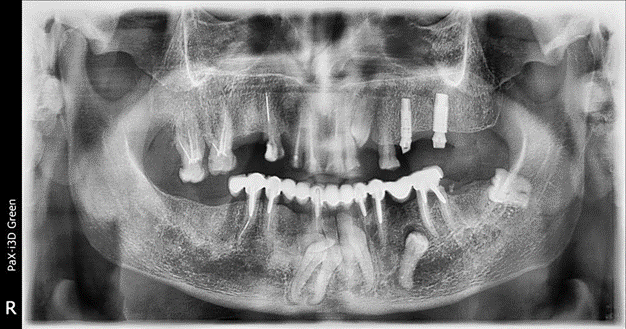

Видно отражение от металла, его дают множественные снимки

Я покажу, как выглядит воспалённая пазуха, металл, запломбированные и незапломбированные каналы, очаги.